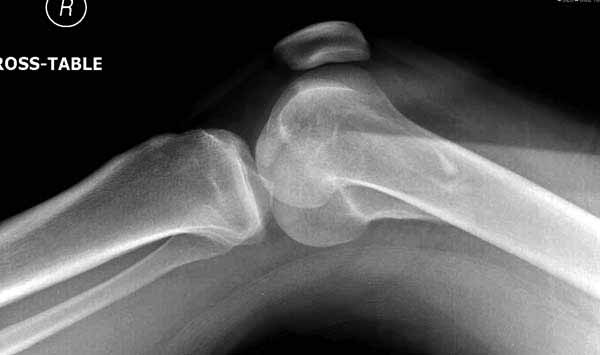

Ответ на эту часть Вашего поста – вложенный файл. Больная оперирована неделю назад по поводу открытого перелома дистального эпиметафиза бедренной кости. После операции она идёт в рентгенкабинет для выполнения послеоперационной контрольной рентгенографии, представленной на слайдах 10 и 11. Узнав, почему её фотографируют, просила передать Вам, Антон, привет.